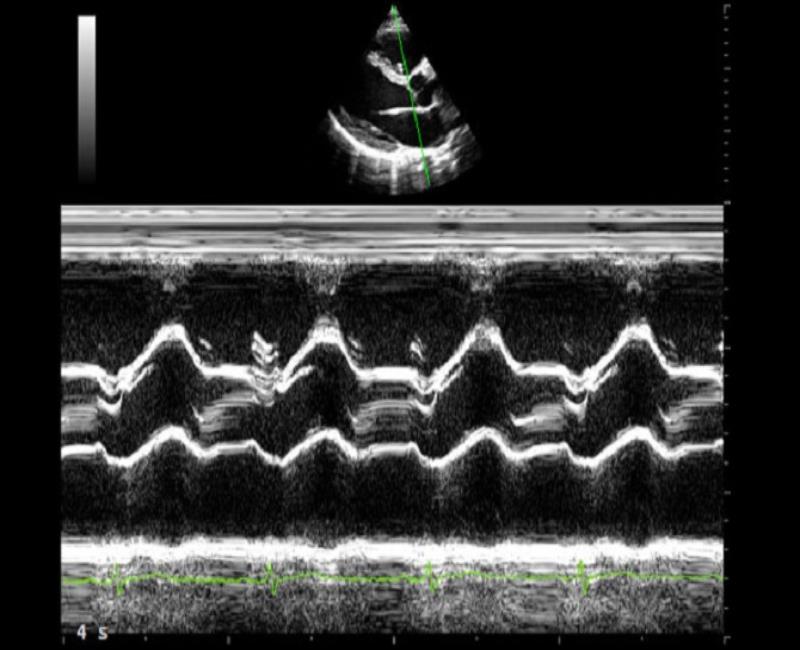

may sieu am mylab x6

CMM - chế độ M-mode, giúp tăng hiệu quả thăm khám trong các trường hợp khó khăn, lên đến 3 đường thời gian thực.